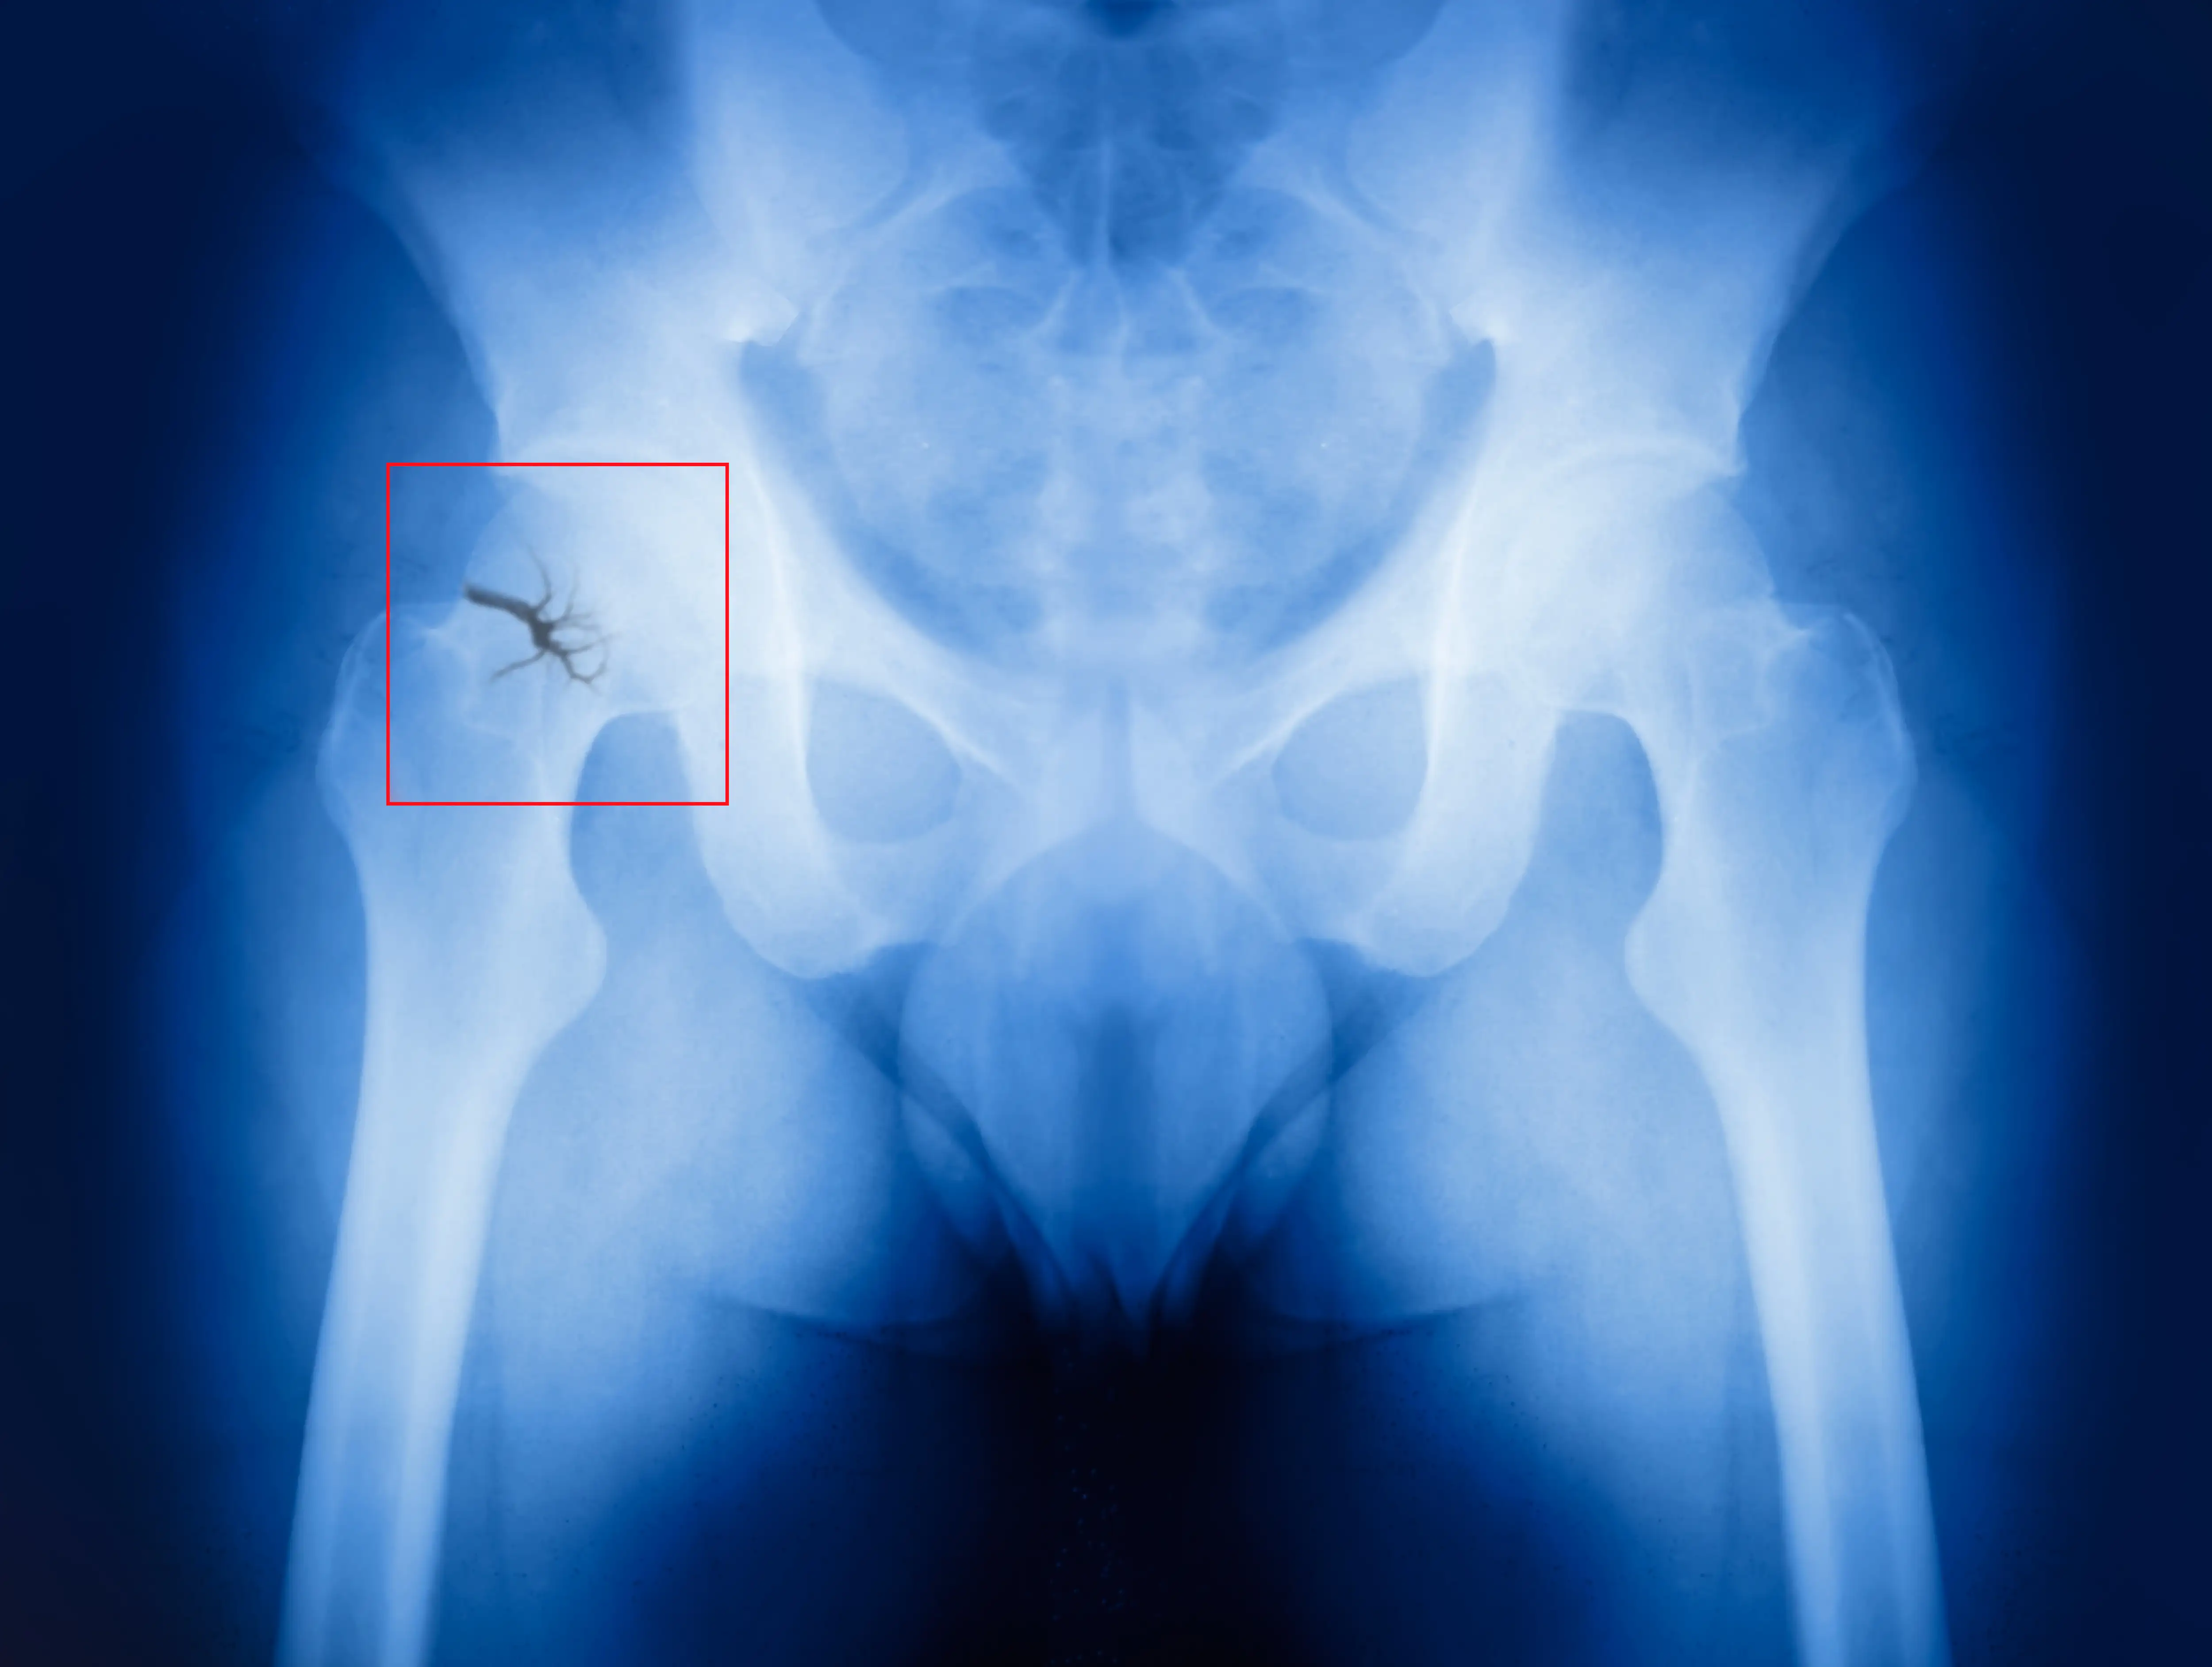

Titanium Elastic Nailing: A minimally invasive solution for pelvic fracture

The titanium elastic nailing system provides a minimally invasive, complication-free surgical solution for restoring the stability of the pelvis lost due to fracture which ensures swift and stable recovery.

The procedure involved temporary fixation of pelvic fractures with the help of a pelvic fixation belt along with traction from the lower limb bone. For specific injuries such as anterior pelvic ring and ilium fractures, closed reduction and intramedullary fixation with TEN were employed. The intraoperative C-arm and O-arm fluoroscopy were utilized to ensure precise placement and alignment of the titanium nails.

Through closed reduction and minimally invasive incisions, pelvic fractures were successfully stabilized with the placement of elastic titanium nails. Complications were notably absent, with all patients experiencing successful wound healing without any nerve or vascular injuries. Moreover, early postoperative mobility was encouraged, enabling patients to engage in functional exercises during the initial stages of recovery, noted the study investigators.